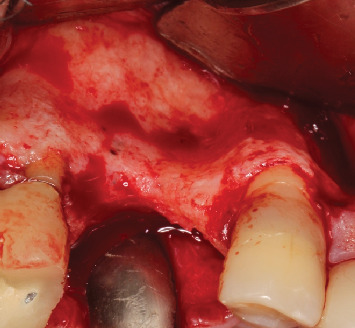

背景:缺牙是一个世界性的问题,影响患者的社会和功能。种植体康复是金标准治疗;然而,可能需要先进行骨重建。杠铃技术是一种引导骨再生技术,推荐用于各种形态的缺陷,允许垂直和水平单向或双向再生,即在颊侧和腭侧/舌侧。本文的目的是报告一例在种植体康复之前的后上颌骨重建,其中杠铃技术与窦提升一起进行。方法:本研究报告了一名77岁男性患者,其右侧第一和第二双尖缺失,并有种植体丢失的历史。最初的CT扫描显示水平和垂直牙槽萎缩,使种植体无法放置。采用鼻窦提升术进行垂直恢复,Barbell技术进行水平再生,使用胶原膜覆盖的异种骨。6个月后,新的CT扫描显示骨容量足够,并根据数字计划引导放置两个植入物。结果:植骨前后的CT扫描显示水平骨增重70%,垂直骨增重33%。重建手术6个月后,植入牙种植体,45天后安装单个冠。在24个月的随访中,未观察到与种植体或假体相关的并发症。结论:在这个临床病例中,这是文献中第一次,这些技术的结合使缺损再生,随后将植入物放置在理想位置并进行假肢康复。

Background: Dental absences are a worldwide issue, affecting patients both socially and functionally. Implant rehabilitation is the gold standard treatment; however, prior bone reconstructions may be necessary. The Barbell Technique is a guided bone regeneration technique recommended for defects of various morphologies, allowing for vertical and horizontal unidirectional or bidirectional regeneration, that is, both on the buccal and palatal/lingual sides. The objective of this paper is to report a case of bone reconstruction in the posterior maxilla prior to implant rehabilitation, where the Barbell Technique was performed together with a sinus lift. Methods: This study consists of a case report of a 77-year-old male patient with the absence of first and second right bicuspids and a history of implant losses in the area. The initial CT scan showed horizontal and vertical alveolar atrophy, making implant placement impossible. Regeneration was performed using a sinus lift for vertical recovery and the Barbell Technique for horizontal regeneration, using xenogeneic bone covered by a collagen membrane. After 6 months, a new CT scan suggested sufficient bone volume, and two implants were guidedly placed based on digital planning. Results: Comparison of CT scans before and after the grafts showed a horizontal bone gain of 70% and a vertical gain of 33%. Six months after the reconstructive surgery, dental implants were placed, followed by the installation of individual crowns after 45 days. At the 24-month follow-up, no complications related to the implants or prostheses were observed. Conclusion: In this clinical case, for the first time in the literature, the association of the techniques allowed the regeneration of the defect, with the subsequent placement of implants in the ideal position and prosthetic rehabilitation.